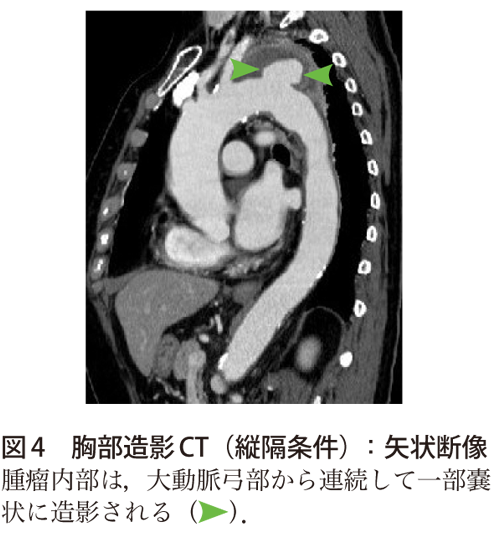

解答 解説 喀血 胸痛を主訴に紹介受診した70歳代女性 実践 画像診断q A 羊土社 レジデントノート 実践 画像診断q A 羊土社 レジデントノート 羊土社